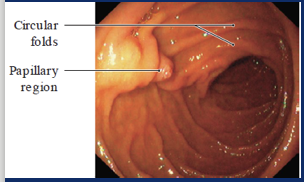

How is the mucosa of the duodenum similar to the stomach?

It has circular folds, which increase surface area for digestion and absorption.

Q

The site where bile and pancreatic juice enter the duodenum, aiding in digestion.